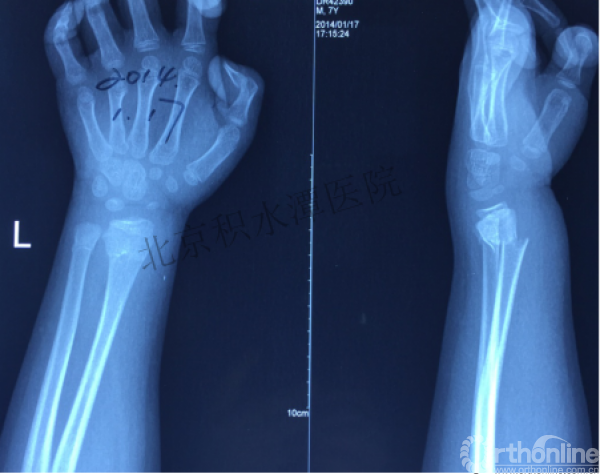

病例分享四

女孩、8岁,桡骨远端骨折

原始损伤

伤后1个月

伤后14个月